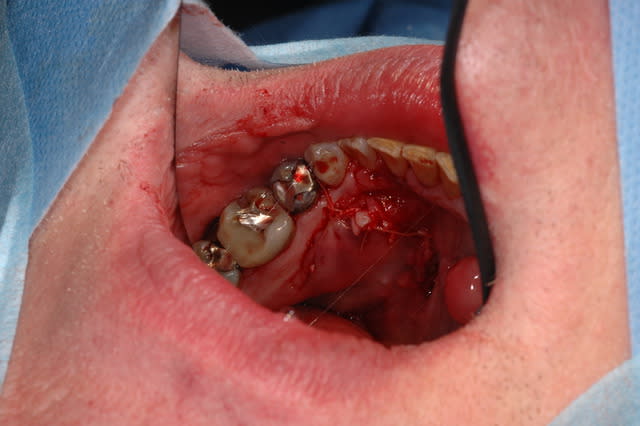

l'anatomie est complexe dans cette région, bravo.

Tu fais cela en France? incision avec laser? scanner pré op?

quel axe pour inciser? Comment gérer l'hématome post op?

Joli travail.